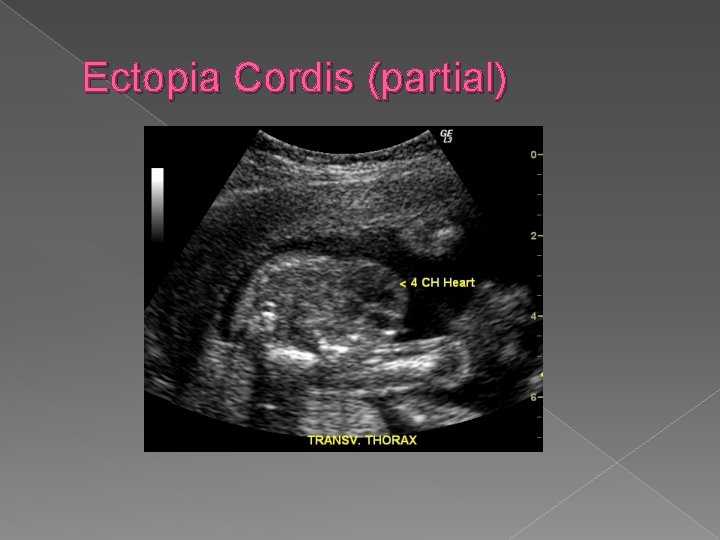

Ectopia Cordis In ectopia cordis, all or part of heart is located outside of chest cavity. It is frequently associated with intra-cardiac anomalies and omphalocele in Pentalogy of Cantrell. Sonographic Findings: � Small thorax � Extension of soft tissue outside thoracic cavity in which cardiac activity is noted.

Ectopia Cordis (partial)